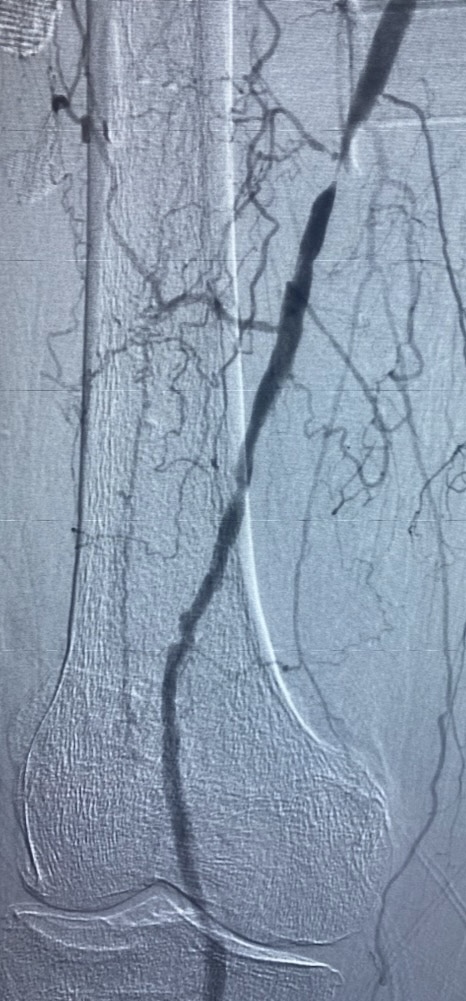

And as we waited with the patient in her post-op recovery, I was struck by the radiographic image we’d just seen – how much it called to mind a river, straining to find its way through a dry and desert land.

“Filled with the Holy Spirit,” I’ve since learned that there’s a different path through the desert available to me – to all of us. Jesus blazed the trail, and by so doing he performed something like an angioplasty on our calcified veins.